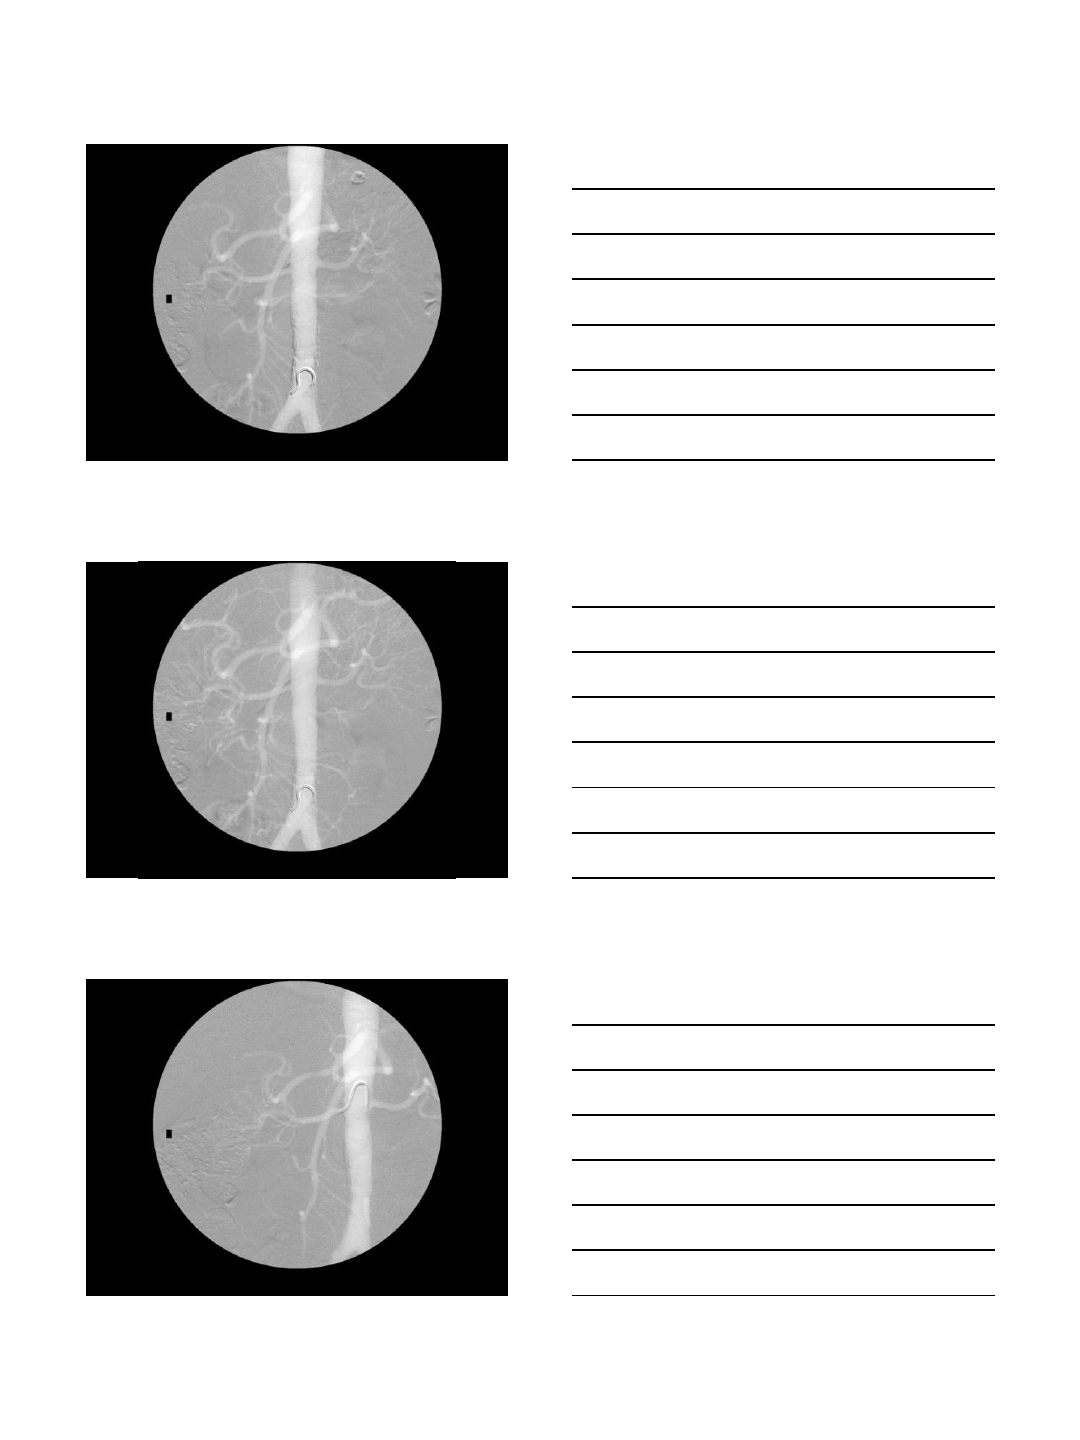

CO2 Portogram in TIPS

TIPS procedures

•AP and oblique views

•Excellent to localize the portal vein

•Wedge injection

•Wedged catheter or balloon catheter

•Gentle injection of 15-20 cc

•Careful in patients with ascites

•Intraparenchymal injection